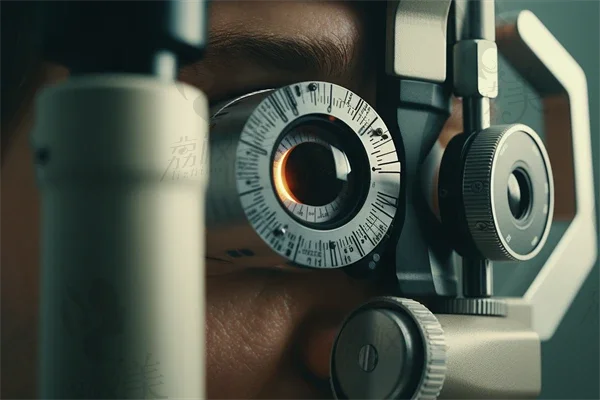

武汉同济医院眼科挂号预约全流程公布:华中地区知名眼科专家坐诊,蔡司VisuMax3.0设备精准诊疗

晋江爱尔眼科医院2026价目表提前公开!全飞秒近视手术18800元起,德国蔡司设备精准矫正

丽江爱尔眼科医院2026近视手术价目表:全飞秒13800元起,ICL晶体植入28000元起

济南爱尔眼科医院预约挂号,地址、电话、营业时间一次性告知,资质齐全,价格表请查阅!

重庆南坪爱尔眼科医院预约挂号流程全揭秘!线上线下多途径,特色检查项目别错过

苏州明基医院眼科医生介绍,简介概览与收费标准透明公开

哈尔滨爱尔眼科医院咨询电话号码是多少?0451 - ***10988 ,2006年建院,占地18000平

呼和浩特地区哪家眼科医院口碑好?呼和浩特光正眼科医院的评价如何?

娄底爱尔眼科医院怎么样?医院简介+青光眼病例分享详细介绍

河南做青光眼的眼科医院有哪些?林州光明眼科医院、安阳林州康目眼科医院、开封市光明眼科医院、灵宝福寿堂眼科医院等医院推荐。

抚州华厦光明眼科怎么预约?多种方式任你选,附各预约渠道操作步骤及医院地址

2025年邯郸眼科医院排名前列,哪家更具实力?探索魏县焕新眼科医院的高度近视眼手术项目,专業与信赖并存。